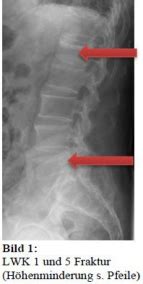

So, what in the world does iideckplattenimpressionsfraktur Lwk 1 actually mean? Well, let’s dissect it. The term refers to a specific type of fracture, but it can be really difficult to find information online. Let’s make sure we find an answer. Each part of the phrase gives us a clue. ‘Fraktur’ is German for ‘fracture’, so we know we’re talking about a break in a bone. However, iideckplattenimpressionsfraktur could mean various things. The ‘Lwk 1’ part likely refers to a location in the spine, specifically the first lumbar vertebra (L1). The complete definition is more complex and depends on the specific terminology of the medical professionals who used it. Understanding this requires a deep dive into medical terminology, but basically, we are referring to a fracture that involves a part of the lumbar spine, specifically the first lumbar vertebra (L1).

This kind of fracture can happen due to a variety of reasons, ranging from high-impact trauma (like a car accident or a fall from a significant height) to more subtle causes such as osteoporosis, which weakens the bones, making them more susceptible to breaks. The nature of the fracture can vary, from simple cracks to more complex breaks involving multiple fragments. The specifics depend on the force involved and the overall health of the bone. Diagnosing it typically involves imaging techniques such as X-rays, CT scans, or MRI scans to visualize the fracture and assess the extent of the damage. Treatment options also vary, and that depends on the severity of the fracture, but can include anything from rest and pain management to more invasive procedures such as surgery to stabilize the spine.